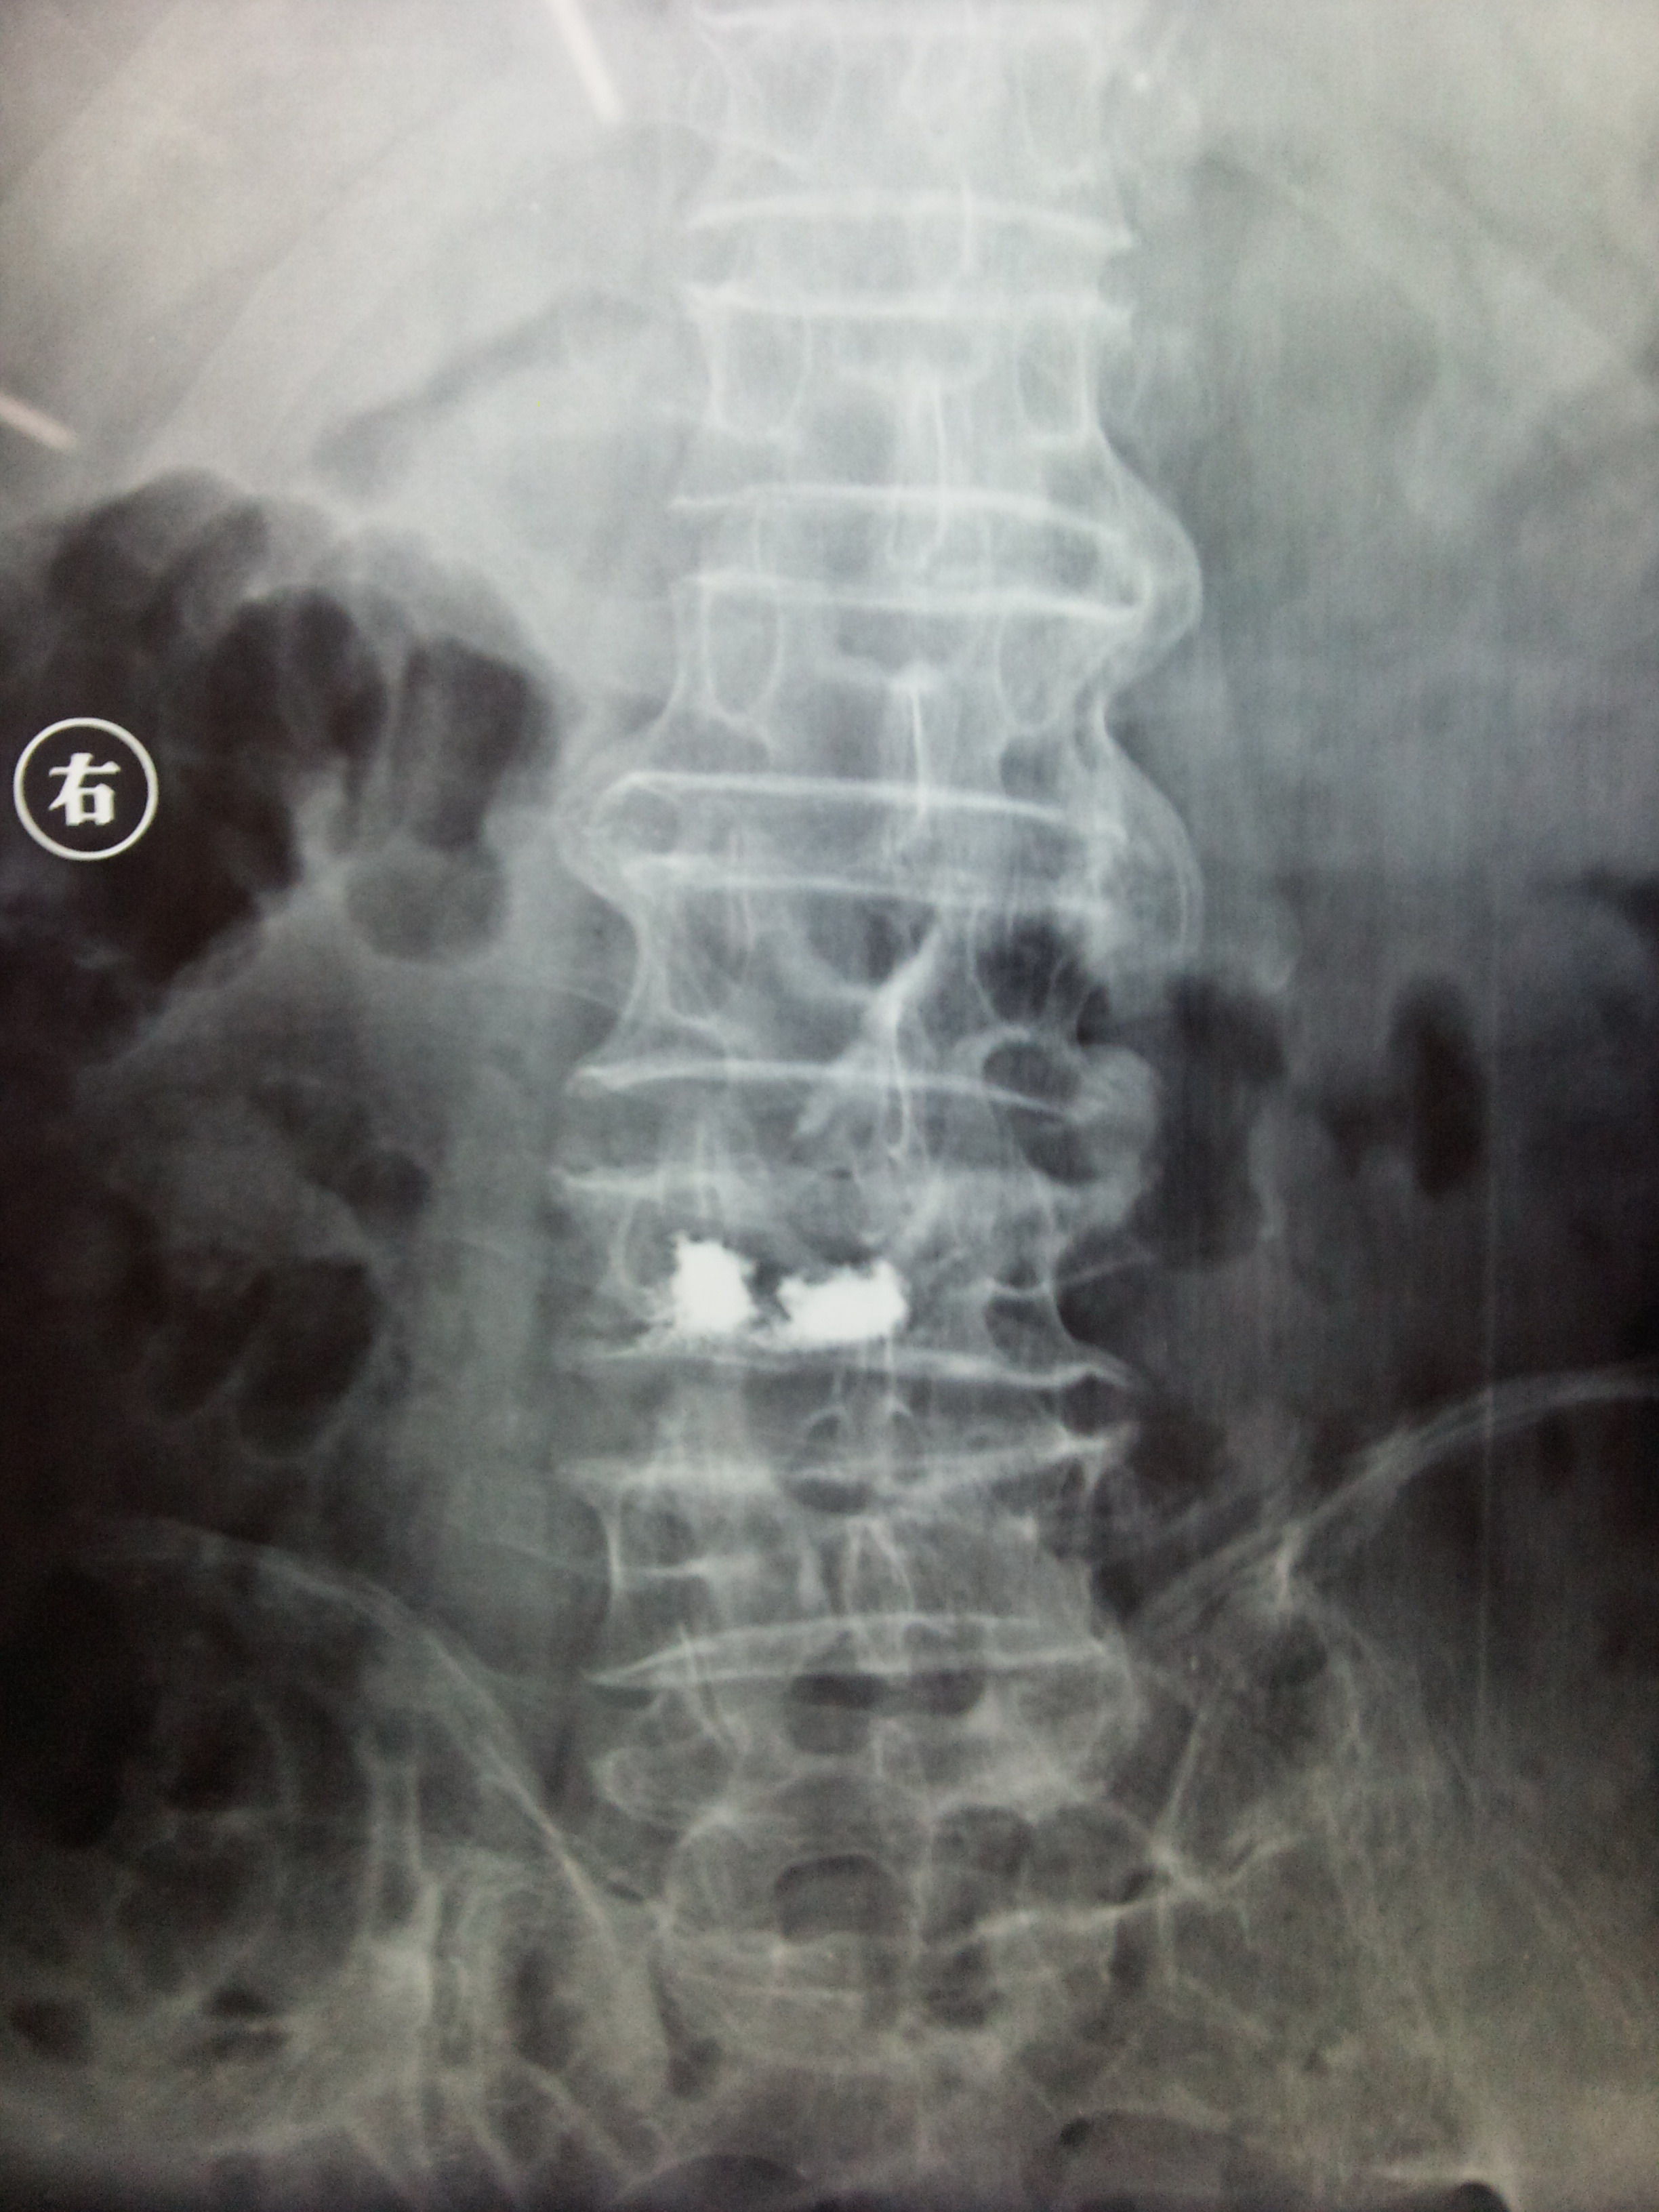

患者,男性,79岁,无明显外伤史致腰痛一个月为主诉入院。入院查体:一般情况好,腰椎活动明显受限,转侧困难,双下肢感觉运动无异常,大小便正常。入院腰椎正侧位片示:第三腰椎压缩性骨折。腰椎MRI示:第三腰椎压缩性骨折(新鲜)。见下图。